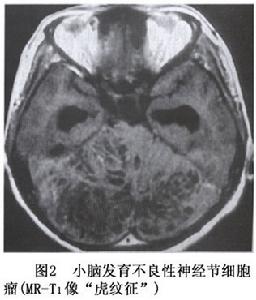

神經元腫瘤和神經元與神經膠質混合性腫瘤圖2

小腦發育不良性神經節細胞瘤(LDD)為小腦神經節細胞過度增生取代顆粒細胞與浦肯野細胞形成的錯構瘤樣病變至2003年文獻上共報導140例。本病由Lhermittle和Duclos在1920年報導,文獻上常稱之為LDD也稱之為小腦錯構瘤、浦肯野瘤或小腦良性肥大。本病可發生在任何年齡,以中青年居多,平均年齡為29歲和34歲,病程長,進展緩慢,主要症狀為顱壓增高、後組腦神經麻痹和小腦損害征。

小腦發育不良性神經節細胞瘤CT為低密度或低與等密度相交替的混雜密度可累及一側小腦半球,偶有鈣化,有輕度占位效應,可幕上腦室擴大及四腦室輕度移位。MRI可見小腦半球異常增大,腫瘤無明顯占位效應,T1像為沿小腦溝排列的低信號和等信號的分層結構T2像為高信號和等信號交錯形成“虎紋征”(圖2,3)。注藥無強化。